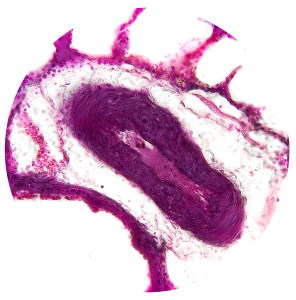

Artery & Vein

Blood Vessels, Trachea & Esophagus